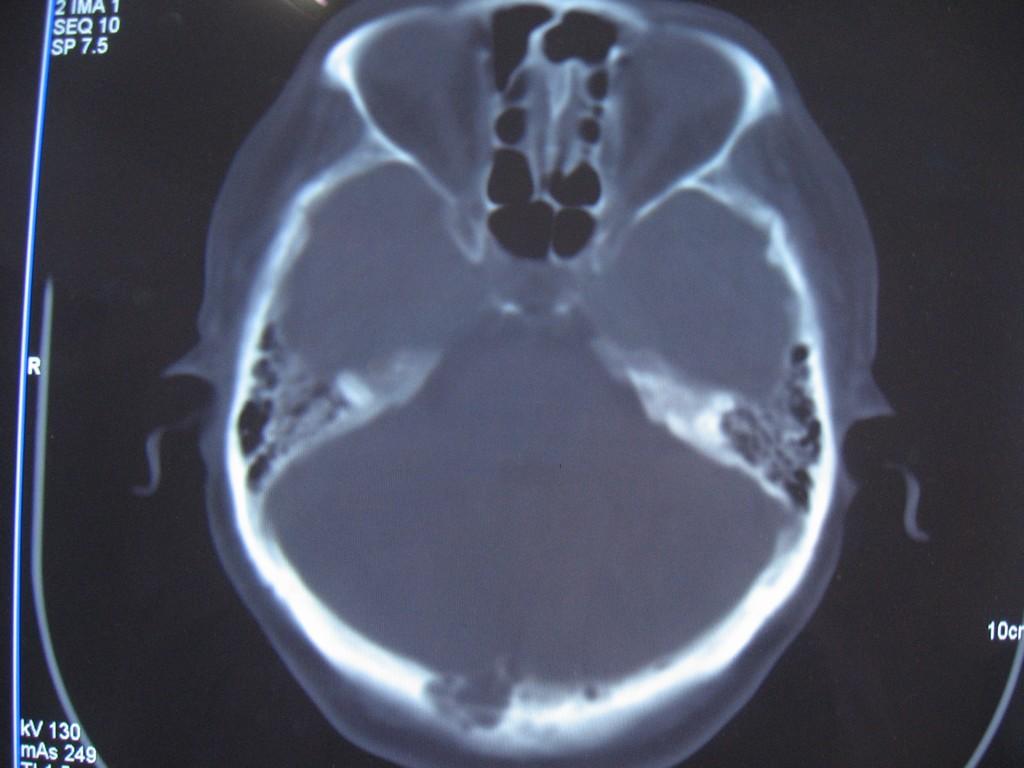

标题: CT22032B:枕骨破坏(从新调整窗宽窗位) [打印本页]

标题: CT22032B:枕骨破坏(从新调整窗宽窗位)

女性病人,53岁,偶尔感枕部针刺样疼痛,ct扫描如下。

蛛网膜颗粒压迹。鉴别:骨巨,嗜酸性肉芽肿,骨髓瘤。

蛛网膜颗粒压迹。

骨巨,嗜酸性肉芽肿,骨髓瘤,动脉瘤样骨囊肿可能

支持蛛网膜颗粒压迹。

支持蛛网膜颗粒压迹,鉴别:骨巨,嗜酸性肉芽肿,骨髓瘤、转移瘤

支持蛛网膜颗粒压迹,嗜酸性肉芽肿发生于30岁以下,基本排除,骨髓瘤、转移瘤多伴有软组织肿块,范围较广。

枕骨蛛网膜颗粒压迹。